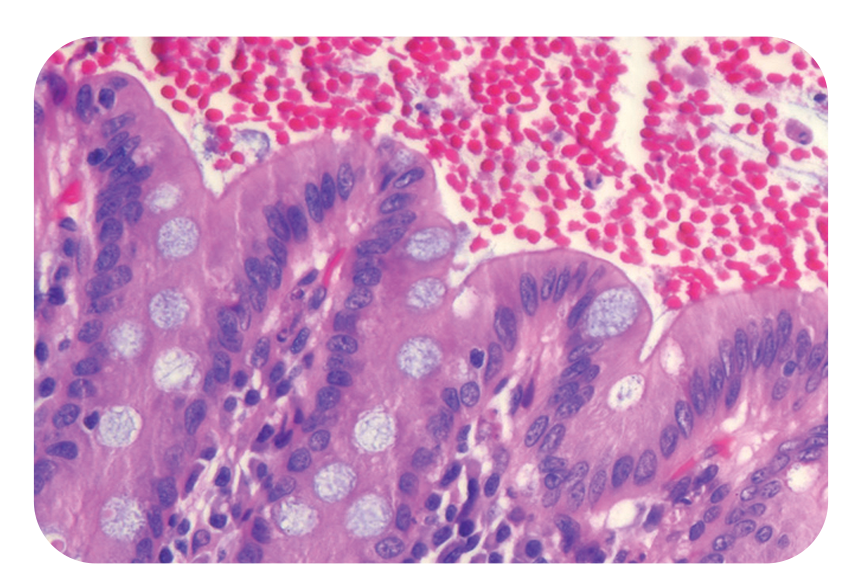

Maintain precision, match your pathologist’s preferences, and explore better H&E staining options with StatLab’s efficient, risk-free Stain Evaluation Program. Whether you want to upgrade from a traditional Gil or Harris hematoxylin to a premium, no-filter alternative—or simply find a StatLab equivalent to your current stain—our experts make the transition seamless.